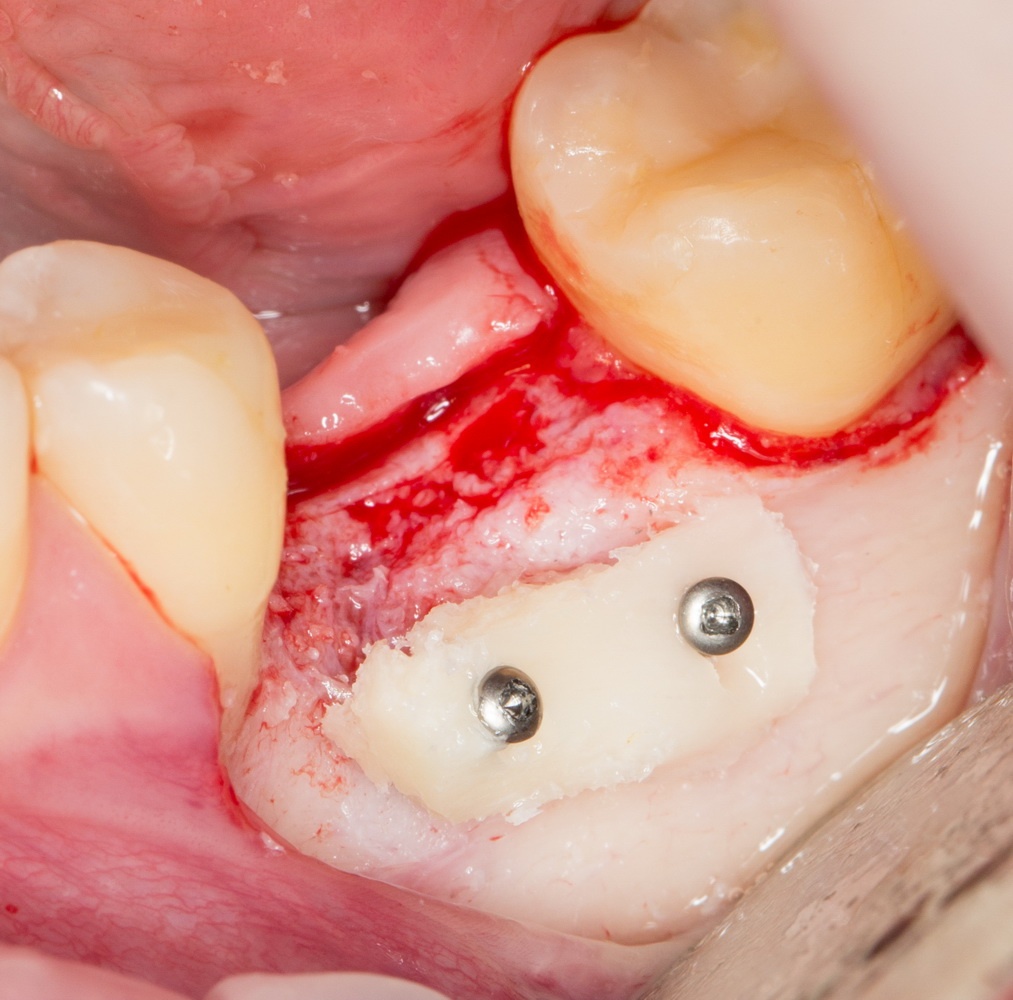

Остеопластика или «наращивание костной ткани» при имплантации — выбор метода и отдаленные результаты.